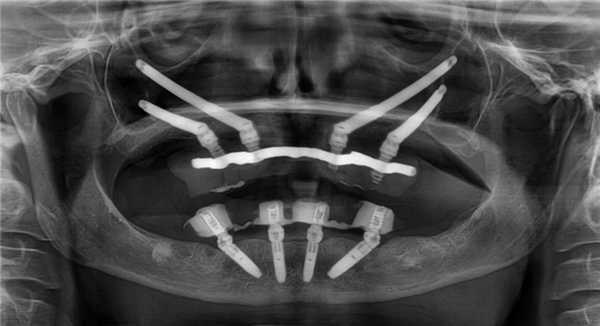

- Рентген-контроль (фото 15)

- По окнчании операции был фиксирован армированный адаптационный протез - фото через 3 суток после операции (фото 16, 17)

Через 6 месяцев после операции первичные адаптационные протезы были заменены на новые адаптационные протезы с армированием (фото 18, 19, 20, 21, 22). Фотографии выполнены через 8 месцев после функционирования второго адаптационного протеза. На снимках видно достаточное количество прикрепленной слизистой, которое удалось создать благодаря правильному позициониравнию имплантатов и естественному заживлению после удаления (фото 23, 24).